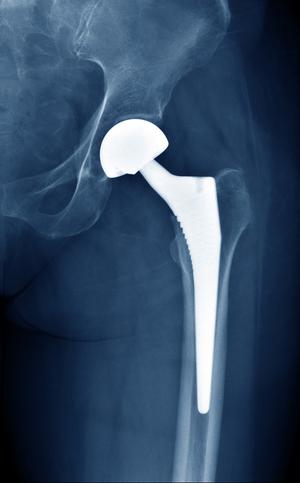

The Joint Replacement Specialists, MedStar Orthopaedic Institute, MedStar Washington Hospital Center

The orthopedic surgeons of the MedStar Orthopaedic Institute at MedStar Washington Hospital Center are comprised of the area’s largest and most experienced team of fellowship-trained, orthopedic specialists who use advanced techniques to treat a wide range of musculoskeletal conditions.